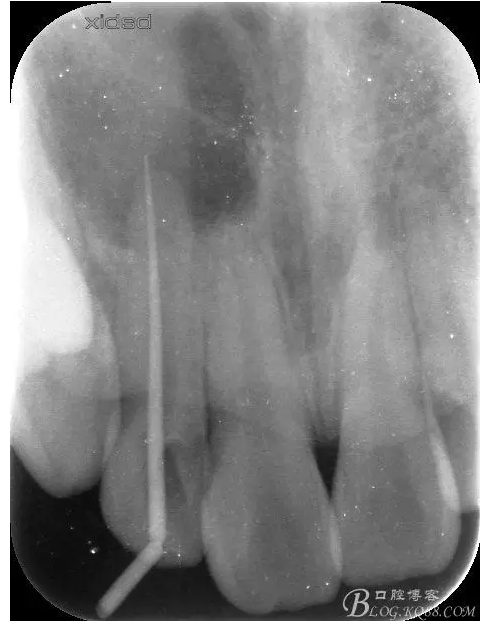

1.術(shù)前的根尖片檢查及根管治療影像:

圖2.根管治療術(shù)后直接局部 麻醉下切開(kāi)、翻瓣,發(fā)現(xiàn)12唇側(cè)骨壁有綠豆大小骨缺損